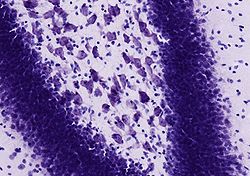

Die Nissl-Färbung, benannt nach Franz Nissl, ist eine histologische Färbetechnik, die insbesondere zur Darstellung von Nervengewebe verwendet wird. Dazu werden histologische Schnitte mit einem Farbstoff wie Kresylviolett, Toluidinblau oder Thionin versetzt. Diese Farbstoffe binden sich an basophile Verbindungen wie RNA und DNA und färben daher die Zellkerne und Ribosomen blau oder violett.[1][2]

Da im Nervengewebe die Ribosomen im Nervenzellkörper konzentrierter als in dessen Fortsätzen (Axon, Dendrit) vorliegen, werden nur die Zellkörper angefärbt. In diesen treten bei der Färbung die so genannten „Nissl-Schollen“ auf, welche dem rauen Endoplasmatischen Retikulum, an das viele Ribosomen angelagert sind, entsprechen.